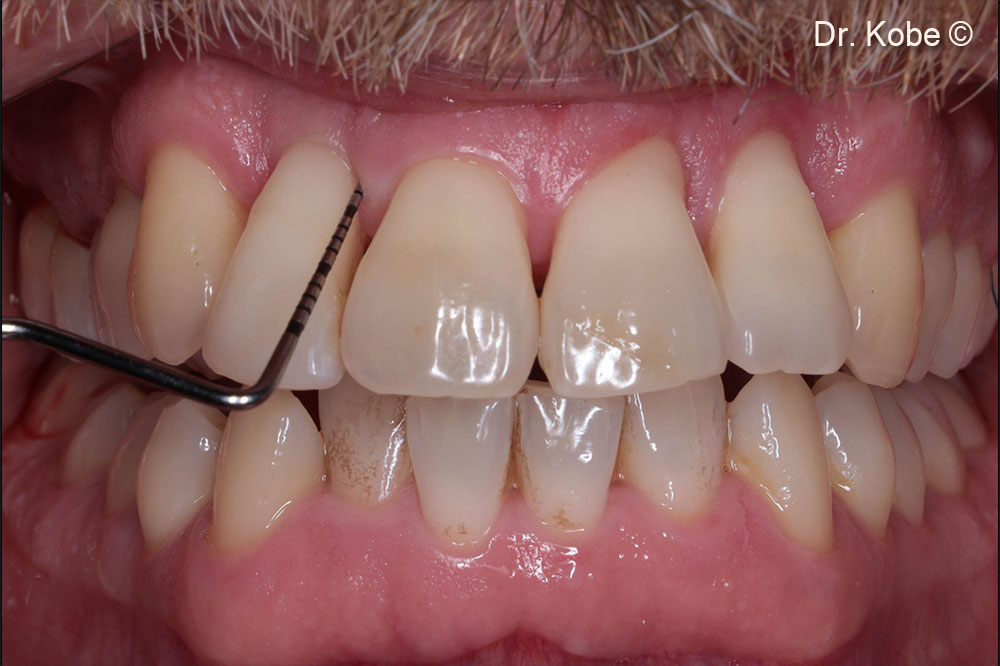

Một bệnh nhân nam (40 tuổi) có biểu hiện tổn thương nha chu nghiêm trọng.

Theo dõi một năm ở góc phần tư thứ nhất

Theo dõi một năm ở góc phần tư thứ hai